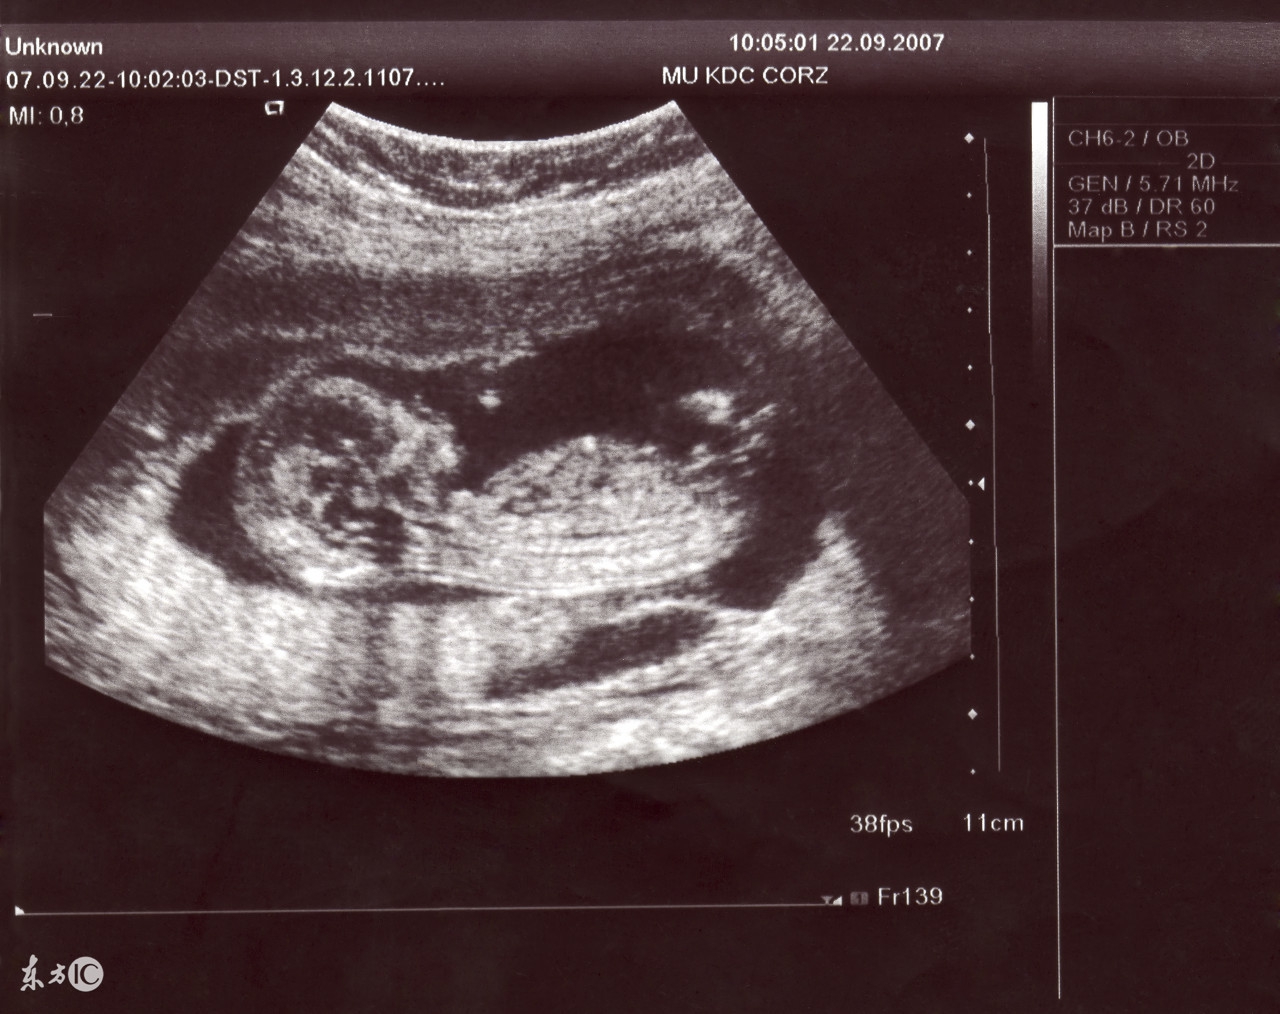

4、二维彩超:黑白色、分辨率比黑白超声高,会用彩色标注心脏、血流等指标;

图片来源于百度图片